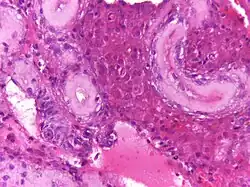

En biopsias realizadas a niños con el síndrome de Klinefelter, se ha observado una disminución en el número de células germinales. No obstante, después de la pubertad se aprecia hialinización y fibrosis de los túbulos seminíferos. Estos cambios histológicos son muy característicos del síndrome, y los cuales originan disminución en el volumen testicular así como aumento de su consistencia. También se observa ausencia de células germinales, hiperplasia y agregación de las células de Leydig, como respuesta a la hiperestimulación por la hormona hormona luteinizante.[23]